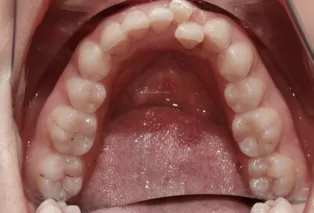

Avant le traitement

Photos intra-orales